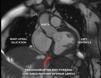

A 62-year-old woman with no personal history of disease was seen due to epigastric pain lasting four days, suffering a right-side pure hemi-motor lacunar stroke with anodyne multimodal CT findings. The ECG tracing evidenced inferior ST-segment elevation with Q waves, and the patient was admitted to intensive care. Transthoracic echocardiography showed septal-basal interventricular communication (IVC) presenting an akinetic inferior aspect with thinning and hyperechogenicity suggestive of pseudoaneurysm with possible contained myocardial rupture (Fig. 1, Video 1). Emergent surgery was discarded due to the neurological condition of the patient and surgical risk due to friability of the tissues. While in wait for the final decision, a cardiac MRI was performed (Fig. 2), after which the patient suffered cardiac arrest with pulseless electrical activity secondary to tamponade, with futile resuscitation efforts (Fig. 3, Videos 2 and 3). Mechanical complications following acute myocardial infarction, while unusual nowadays, remain a potentially fatal and time-dependent disorder in which imaging techniques such as echocardiography continue to play a key role.